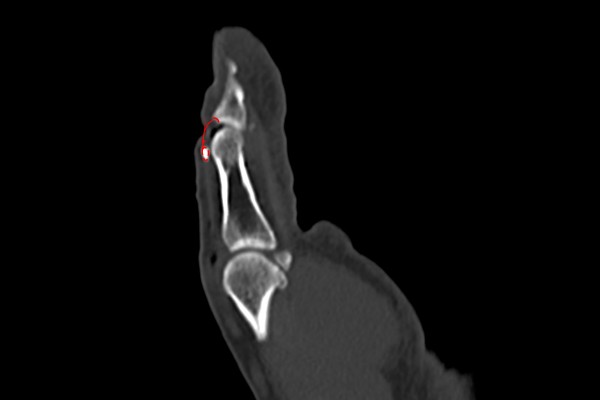

타병원에서 촬영한 X-RAY를 보면 골절로 인한 뼛조각이 확인됩니다.

CT영상을 확인했을 때 역시 뼛조각이 확인되며, 원래 있어야 할 위치에서 떨어져 내려와 있는 것이 확인되어 손가락 안들림, 엄지 망치수지 골절(Open mallet Fx. 1st DP base hand Rt.)을 진단하였습니다.